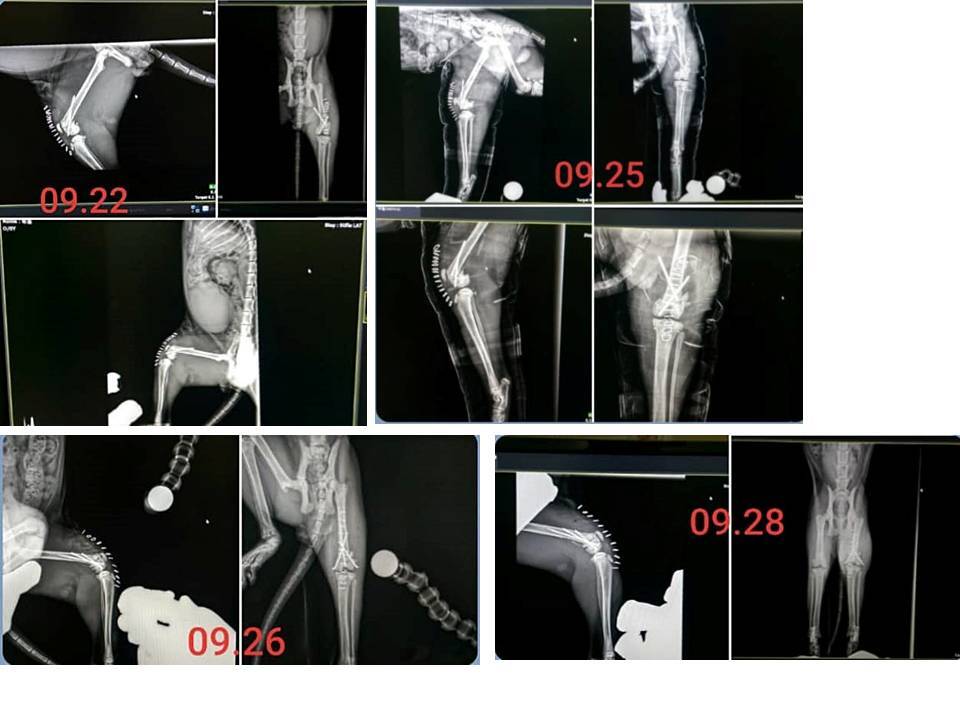

9月間發現咪嚕後腳無法著地且腫起,

立即帶往醫院,

經X光檢查後,發現骨頭斷裂了,

應是從高處躍下的姿勢不正確因此傷及,

在安排時間後醫師進行了骨折內固定手術,

手術順利完成,但術後須住院觀察、更換包紮及清理傷口,

住院至10月4日醫師評估已可出院自行照護隨即出院。

本筆醫助為咪嚕在沐恩醫院9月22日至10月4日的醫療費用,請大家一起幫忙,謝謝大家。